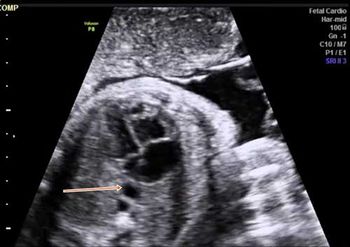

QUIZ: These images are of the fetal heart reveal an abnormality. Can you identify it?